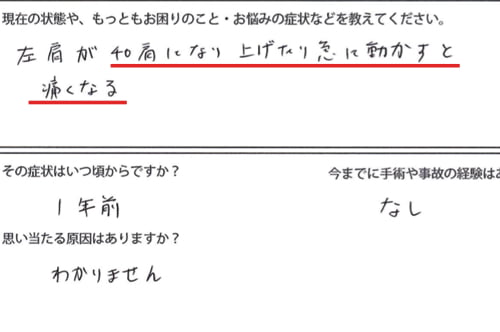

腕を上げる際に、この辺りまで上げると肩付近に痛みが出てしまいます。

腕の上がり方を見てみると、真上のは上がらないものの

施術後すぐに、腕はここまで上がるようになりました。